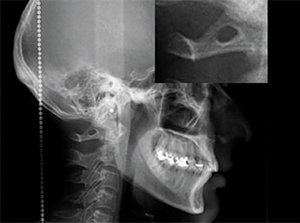

Clinicians should consider the possibility of an arcuate foramen with patients complaining of vertigo, headache, shoulder-arm and neck pain. Cervical spine radiography is a simple and useful technique to determine the presence of arcuate foramen. (Figure 1)

Figure 1: Cervical X-ray of the arcuate foramen. The portion of the radiograph showing the structure has been enlarged at top right for viewing.